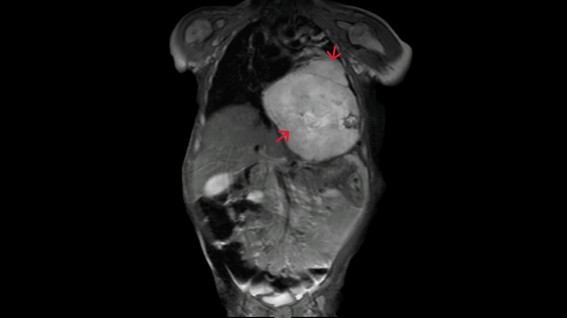

Serologies were negative, blood cultures pending, and neuron-specific enolase elevated (184.6 ng/mL). Cranial computed tomography (CT) was normal. Lumbar puncture revealed normal cytochemical analysis; cerebrospinal fluid (CSF) viral studies were negative, and bacterial culture of CSF was pending. Intravenous ceftriaxone and acyclovir were started. Due to clinical suspicion of OMS, the patient was admitted for further evaluation. MRI revealed a large mass occupying the lower two-thirds of the left hemithorax, without peripheral invasion, suggestive of neuroblastoma or teratoma (Figure 1). He was subsequently transferred to a tertiary center, where imaging favored neuroblastoma.

Figure 1. Thoraco-abdominal-pelvic magnetic resonance imaging showing neuroblastoma in the coronal plane.